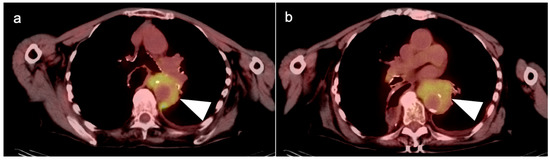

5. Cholangiocarcinoma